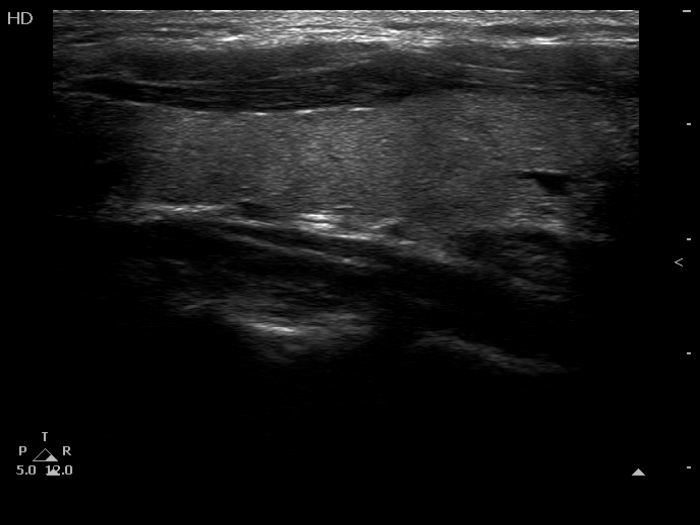

The composition of the nodule - case 1511 (ultrasonographic picture 9)

Left lobe, longitudinal scan.